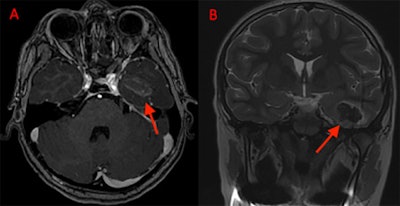

At his two-month follow-up, an MRI showed a collapsed porencephalic defect at the site of his trauma. A little more than three months after the initial presentation, he followed up again with neurology. He is being managed with 300 mg of oxcarbazepine twice daily and only one seizure in the preceding month, the authors wrote.

(A) An axial T2 SSFSE and (B) an axial T2 GRE MRI at two-month follow-up shows the collapsed porencephalic defect in the left temporal lobe.